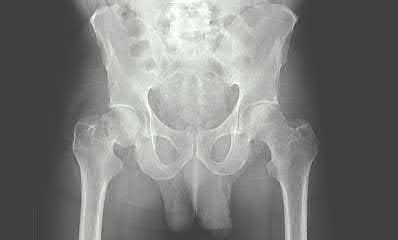

A 35 year-old female presents after prolonged extrication from a motor vehicle collision complaining of severe pelvic pain. Physical examination reveals diminished perianal sensation. She is otherwise neurologically intact. Figures A through D are radiographs and representative CT cuts of her injury. Which of the following nerve roots has likely been injured by the acute trauma?

The clinical scenario is consistent with a high-energy sacral fracture. The radiographs in figures A and B demonstrate a sacral fracture with posterior displacement of the right hemipelvis seen on the inlet view. Figures C and D are axial and sagittal CT images which show a displaced fracture of the right

hemisacrum along with a transvere fracture component through the S3 body . Diminished perianal sensation is concerning for an S2 nerve root injury.

Mehta et al reviewed the current management of sacral fractures. They note that the S1 and S2 nerve roots are more likely to be injured with sacral fractures as they occupy 1/3 to 1/4 of the neural foramina, as opposed to S3 and S4, which only occupy 1/6 of the neural foramina.

Robles reviewed the current literature to ascertain principles of evaluation and treatment for transverse sacral fractures. The author notes that injury to nerve roots S2 to S5 is manifested by impairment of urinary and anal continence and sexual function.

The first illustration demonstrates the sacral nerve root dermatomal distribution. The second shows a pelvic cadaver dissection demonstrating the sacral nerve roots as they exit the foramina.